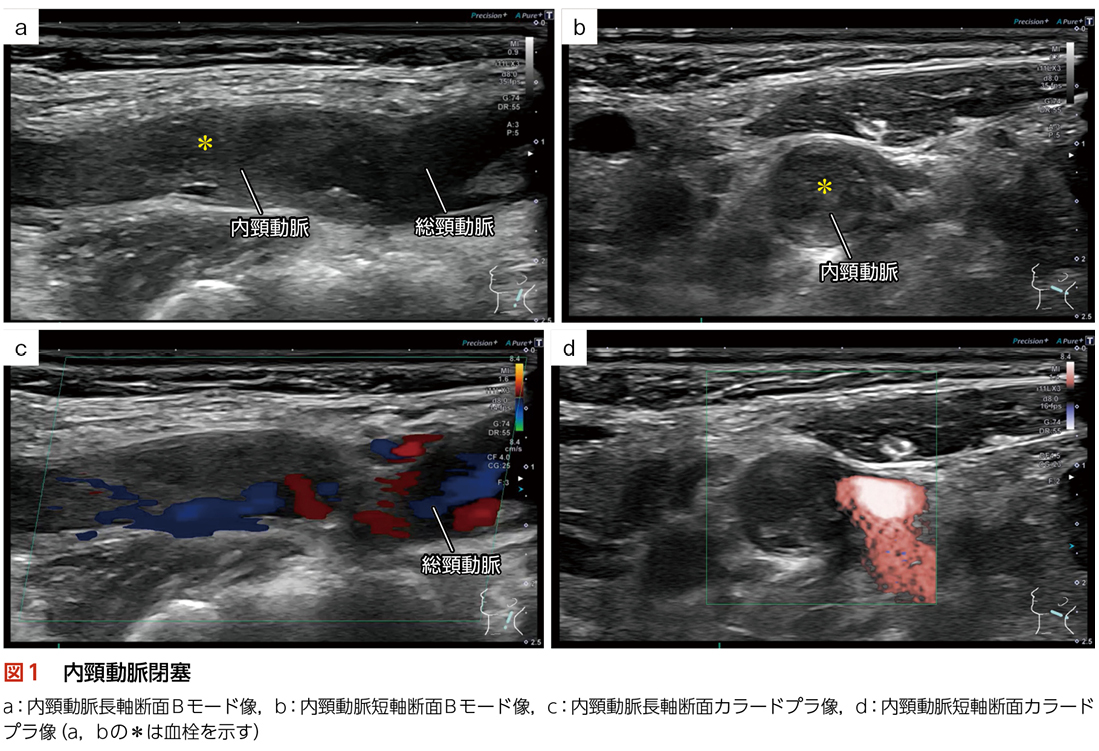

◆主訴:左片麻痺

◆現病歴:起床時より左片麻痺が出現

◆検査目的:塞栓源検索,動脈硬化評価を目的として検査実施